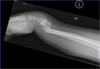

**Smith's fracture (reverse Colles' fracture)** 1. Volar angulation of distal radius fragment (Garden spade deformity) 2. Caused by falling backwards onto the palm of an outstretched hand or falling with wrists flexed

Smith Fracture ## Footnote Typically FOOSH back of hand Extra-articular radial # with volar (anterior / palmar) angulation and displacement